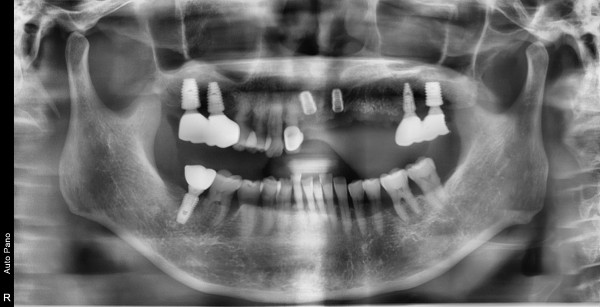

64세 여/ 전치부 발치 및 치조골 이식술 후 임플란트 식립